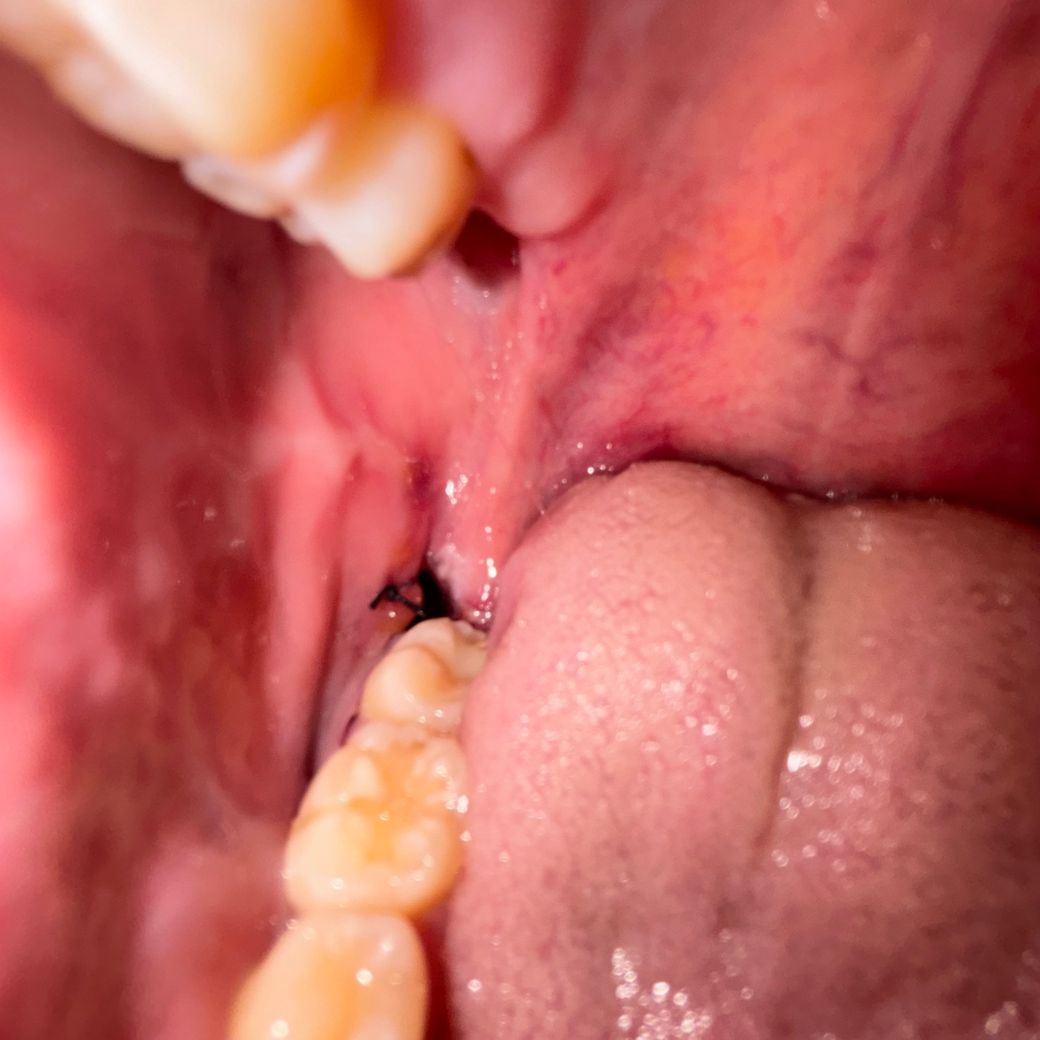

사랑니 발치 실밥 끊어짐 사진 첨부하였습니다!

사랑니 발치 실밥 끊어진 거 같은데 병원 가야 하나요?

발치한지는 하루 됐습니다.....

• 1번 째 사진

단순히 실밥이 끊어지고, 상처부위가 버리지지 않은것으로 보입니다. 이 경우에는 치과에 다시 방문히지 않으셔도 되며, 해당부위 염증이 덧나지 않도록 소독용 헥사메딘 가글액으로 가글하여 관리하길 권합니다.

실밥이 끊어진건 아닌거 같고, 잇몸의 붓기가 가라 앉게되면서 실밥이 느슨해진거 같으니 너무 걱정하지 않으셔도 될것같습니다.

사진상 명확히 구분되진 않으나 봉합실이 끊어진 건 아닌 것 같습니다. 발치 후 주의사항 잘 지키시고 봉합실 푸는 다음 약속때 맞춰 가시면 되겠습니다.